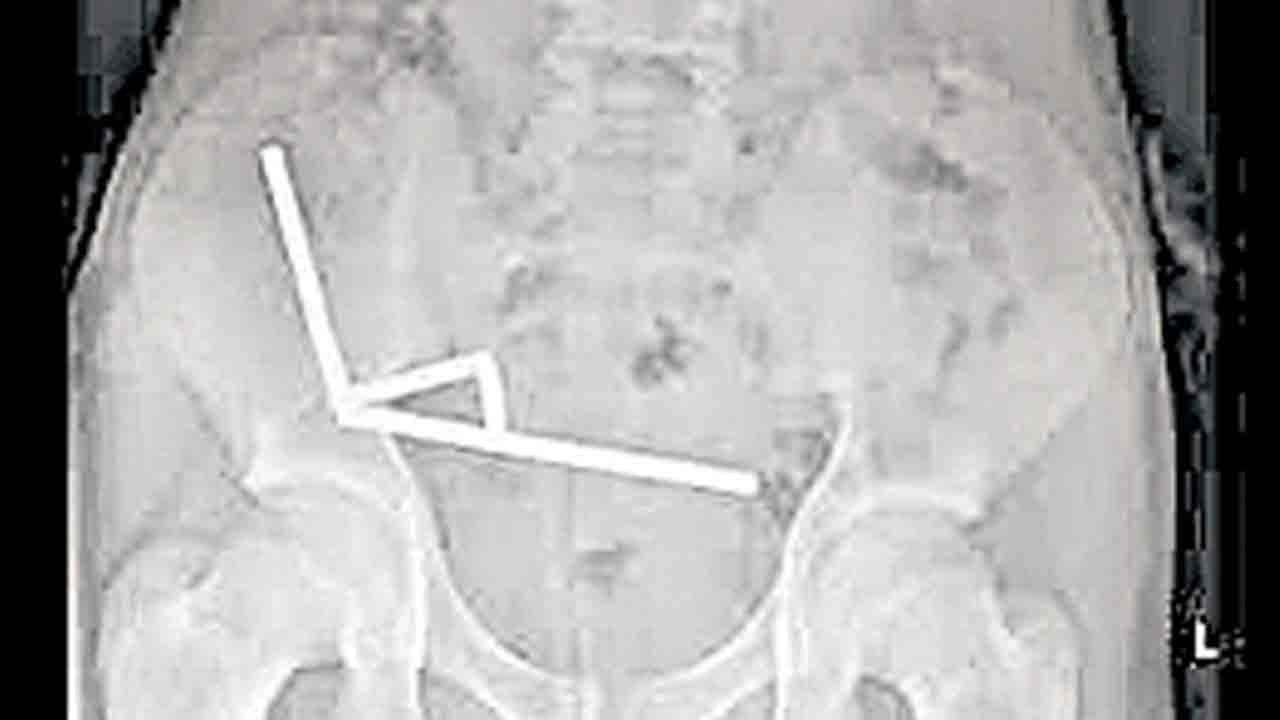

వెల్లింగ్టన్: న్యూజిలాండ్లో ఒక బాలుడి కడుపు లోంచి 100 అయస్కాంతాలను (Magnets) డాక్టర్లు శస్త్రచికిత్స చేసి బయటకు తీశారు. 13 ఏండ్ల ఆ బాలుడు వాటిని ఆన్లైన్లో కొనుగోలు చేసి మింగినట్టు గుర్తించారు. ఆగకుండా కడుపులో నొప్పి రావడంతో ఆ బాలుడిని దవాఖానకి తరలించారు. ఎక్స్రే తీసి చూడగా, అతని కడుపులో అయస్కాంతాలు 80 నుంచి 100 వరకు ఉన్నట్టు గుర్తించారు.

ఆయస్కాంతాలు అతడి పేగుల్లో, పెద్దపేగుల్లో చిక్కుకుపోయాయని, వాటి ఒత్తిడి కారణంగా ఆ ప్రాంతాలు దెబ్బతిన్నట్టు డాక్టర్లు తెలిపారు. అయస్కాంతాల అమ్మకంపై 2013 నుంచి నిషేధం ఉన్నా ఆన్లైన్ కంపెనీ టెము ద్వారా వాటిని విచ్చలవిడిగా అమ్ముతున్నారని, ఆ కంపెనీపై చర్య తీసుకోవాలని ఆ దేశ ప్రజలు డిమాండ్ చేస్తున్నారు.